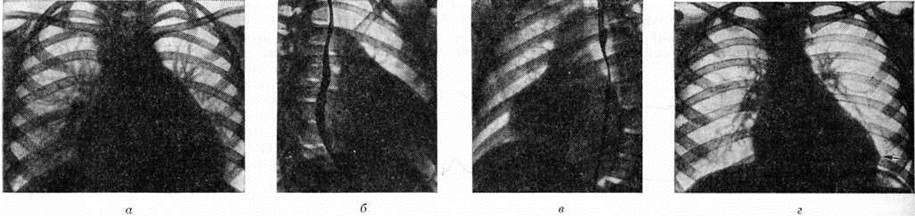

Таким образом, рабочая классификация позволяет оценить Ревматизм как патогенетически многоплановую болезнь у конкретного больного с дифференциацией по степени активности, характеру течения, с указанием на первичный или возвратный характер ревматического процесса, что в значительной мере помогает врачу в определении тактики ведения больного и организации индивидуализированного диспансерного наблюдения. Основные клинические проявления ревматизма, его течение и диагностикаНесмотря на полиморфизм клинических проявлений Ревматизм, в его развитии отмечены чёткие закономерности, позволяющие выделить заболевание как строго очерченную нозологическую форму. К ним, в частности, следует отнести связь Ревматизм со стрептококковой инфекцией (наличие скрытого периода между окончанием инфекции и начальными симптомами болезни). Для Ревматизм характерны также тенденция к полисиндромности клинических проявлений, существование типовых вариантов начала и течения заболевания, наличие в клинической картине впервые выделенных А. А. Киселем «абсолютных признаков ревматизма» и, наконец, склонность Ревматизм к обострениям и рецидивам. В значительной части случаев классические острые формы Ревматизм заканчиваются полным выздоровлением. Вместе с тем, главным образом при затяжном течении и рецидивах Ревматизм, могут возникать условия, способствующие последующему переходу болезни в хронический, торпидный, часто обостряющийся процесс. А. И. Нестеров (1973) выделяет в развитии ревматического процесса три периода. Первый (скрытый) период продолжается обычно 2—4 недели после окончания стрептококковой инфекции до начальных проявлений ревматической атаки. Он характеризуется процессами токсикоинфекционного повреждения соединительнотканных структур и иммунологической перестройкой организма в ответ на стрептококковое антигенное воздействие. Клинически этот период протекает или бессимптомно, или с проявлениями, свойственными периоду затянувшейся реконвалесценции. Второй период — период гиперергических тканевых реакций с отчётливыми и характерными клиническими проявлениями болезни (ревматическая атака). Важно отметить, что и на фоне адекватной антиревматической терапии обратное развитие клинических симптомов атаки не происходит одномоментно. После исчезновения ярких воспалительных проявлений заболевания закономерен переход его в скрытую фазу с постепенной нормализацией иммунологических и биохимических показателей. Третий период проявляется многообразными формами возвратного Ревматизм Он характеризуется определённой тенденцией к дальнейшему нарушению и качественным изменениям защитных и компенсаторных реакций с нарастанием иммунологических расстройств, прогрессированием дистрофических процессов. Клинически значительно чаще обнаруживаются затяжной и непрерывно-рецидивирующий варианты течения болезни, приводящие к прогрессирующей недостаточности кровообращения и другим осложнениям, определяющим неблагоприятный исход Ревматизм Выделяют также первичный и возвратный Ревматизм Первичный Ревматизм, как правило, возникает в детском и юношеском возрасте, характеризуется преимущественно острым и подострым вариантами течения болезни (у 88% больных, по данным 8. П. Анненковой, 1981). Отмечается четкая возрастная закономерность в развитии первичного Ревматизм: грудные дети, как правило, не болеют, двух-, трёхлетние заболевают крайне редко, а в последующие годы заболеваемость возрастает, достигая максимума у детей 7—14 лет и подростков. В детском возрасте обычно половых различий в заболеваемости первичным Ревматизм не наблюдается, среди подростков чаще Ревматизм заболевают лица женского пола. К начальным клиническим проявлениям острого первичного Ревматизм относится лихорадка, мигрирующий полиартрит (у 50—60% заболевших, по материалам Института ревматологии АМН СССР) или выраженные артралгии, относительно редко — серозит и признаки поражения других органов и систем. Отмечается взаимосвязь между высокой лихорадкой, полиартритом и серозитом. Кардит, даже выраженный, может протекать лишь с умеренным повышением температуры или при нормальной температуре тела. Характерна полная и быстрая обратимость полиартрита и относительно благоприятное течение висцеральных проявлений Ревматизм под влиянием противовоспалительной терапии. Определяются высокие титры противострептококковых антител и значительное повышение лабораторных показателей активности воспаления. Первично-хронические варианты течения Ревматизм относительно редки. Остаётся не уточнённым вопрос об удельном весе первично-латентного течения в структуре заболеваемости Ревматизм Первичному Ревматизм свойственны генерализованные экссудативные воспалительные реакции, однако за последние 20—25 лет (с конца 50-х годов) отмечена эволюция первичного Ревматизм в сторону смягчения ярких экссудативно-гиперергических форм заболевания. Сравнительно редки теперь острые воспалительные поражения одновременно всех оболочек сердца (панкардит), первичные экссудативные плевриты, перикардиты, острые менингоэнцефалиты. Значительно реже выявляются первичные ревматические пневмонии, кольцевидная эритема, ревматические узелки, мягче протекает ревматическая хорея. Отмечаются возрастные особенности течения первичного Ревматизм Так, у дошкольников преобладает затяжное течение, а в младшем школьном возрасте — подострое. Наибольшую опасность представляет 12—14-летний возраст, при котором чаще, чем в других возрастных группах, обнаруживается острое и подострое, а иногда п непрерывно-рецидивирующее течение. Вместе с тем в этом, как и в более старшем возрасте (15 —18 лет), нередко наблюдается первично-латентное течение с вовлечением в процесс клапанов сердца. Возвратный Ревматизм как проявление третьего периода развития заболевания характеризуется особой склонностью к обострениям и рецидивам, прогрессирующим нарушениям трофики и регуляторных процессов с преобладанием затяжных, непрерывно-рецидивирующих вариантов течения. По материалам института ревматологии АМН СССР (В. А. Насонова, И. А. Бронзов, 1978), среди 200 больных первичным Ревматизм острое и подострое течение болезни отмечено у 77,5%, непрерывно-рецидивирующее — у 2,5%, а затяжное — у 20%. В то же время среди 200 больных возвратным Ревматизм эти показатели составляют соответственно 28%, 11% и 61%. Подобно первичному, возвратный Ревматизм может проявляться полиартритом, вовлечением в воспалительный процесс серозных оболочек, лёгких, нервной системы и других органов. Однако наиболее постоянным является кардит, клиническое течение которого чаще всего определяет характер течения возвратного Ревматизм в целом. При этом, по мере возникновения новых обострений, наряду с урежением частоты и ослаблением выраженности поражения суставов отмечается прогрессивное утяжеление сердечной патологии за счёт нарастания поражения клапанов и миокарда сердца. Значительно чаще встречается непрерывно-рецидивирующее течение. Ревматический кардит (ревмокардит)Ревматический кардит — ведущее проявление активного Ревматизм, определяющее тяжесть течения и прогноз заболевания. К особенностям ревматического кардита относится тенденция к последовательному или одновременному воспалительному поражению миокарда, эндокарда и перикарда (смотри полный свод знаний: Панкардит). В связи с трудностями разграничения поражения отдельных оболочек сердца в клинической практике широкое распространение получил обобщённый термин «ревмокардит». Первичный ревмокардит, по данным разных исследователей, распознается у 80—90% детей и у 95— 100% взрослых, заболевших Ревматизм Несмотря на существование некоторых возрастных особенностей, принципиальных различий в клинических проявлениях первичного ревмокардита у детей, подростков и взрослых не отмечается. Симптоматика ревмокардита во многом определяется преимущественным поражением той или иной оболочки сердца — миокарда, эндокарда и перикарда. Существенное влияние на характеристику ревмокардита оказывают выраженность изменений со стороны сердца, степень общей активности ревматического процесса и характер течения заболевания. Ревматический миокардит является основным, а нередко и единственным признаком болезни. Так, у 40—60% больных Ревматизм в начале заболевания (особенно при остром течении) изменения со стороны сердца укладываются в картину изолированного миокардита (смотри полный свод знаний), морфологически варьирующего от диффузного до очагового. Диффузный миокардит с ярко выраженными клиническими проявлениями встречается в 70—80-е годы реже, чем 20—30 лет тому назад, и наблюдается преимущественно у детей 12— 14 лет и подростков. Преобладающим является умеренно и слабо выраженный миокардит. У больных с ревматическим миокардитом нередко отмечаются нарушение общего состояния, слабость, одышка, кардиалгии, сердцебиения. Выраженность субъективных неприятных ощущений обычно небольшая, поэтому они чаще выявляются при тщательном целенаправленном опросе больных. К ранним объективным симптомам относится изменение частоты сердечных сокращений в покое — тахикардия (смотри полный свод знаний), брадикардия (смотри полный свод знаний) и дыхательная аритмия сердца (смотри полный свод знаний); увеличение размеров сердца (от незначительного до выраженного), ослабление или глухость тонов сердца (смотри полный свод знаний), возникновение трёхчленного сердечного ритма. На фонокардиограмме обычно находят снижение амплитуды I тона, его деформацию, расщепление и уширение, так называемые патологические III и реже IV тоны (высокоамплитудные, записываемые в средне и высокочастотном спектре, с широкой зоной регистрации), слияние которых создаёт клиническую картину суммационного ритма галопа (смотри полный свод знаний: Галопа ритм).